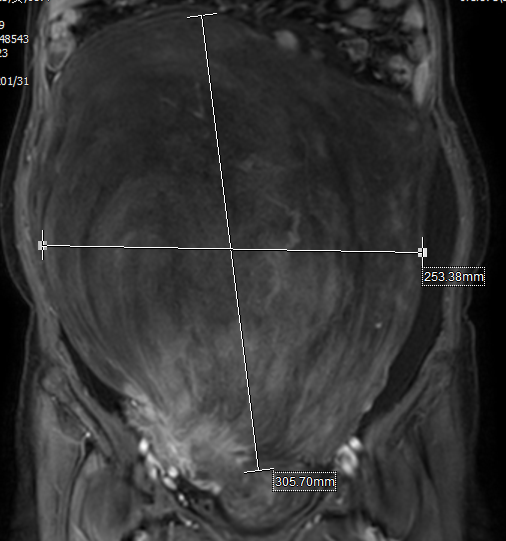

患者,女性,57岁,以“发现腹部包块增大半年”收住医院妇科,入院后查体显示腹部膨隆,如足月妊娠大小,腹部可触及一约35*25cm大小包块,质硬,活动性差,上界达剑突,下界至盆底,行MRI检查提示:盆腹腔巨大占位性病变,大小约144*258*347mm大小,多考虑间叶源性肿瘤性病变,肌源性肿瘤可能性大。